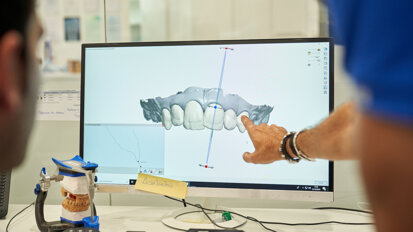

Po zakończeniu skanowania następuje przesłanie informacji za pomocą internetu do laboratorium.Tutaj w oparciu o cyfrowy zapis pola protetycznego są jednocześnie wykonywane 2 czynności: drukowanie modelu stereolitograficznego (Ryc. 7), które zastępuje standardowy model gipsowy w stomatologii cyfrowej, a także projektowanie (Ryc. 8 i 9) i następnie wycinanie czapki (Ryc. 10) stanowiącej podbudowę do napalanej ręcznie porcelany w kolejnym etapie produkcji odbudowy protetycznej.

Kolejne etapy pracy (napalanie porcelany na wycięte przez frezarkę podbudowy, Ryc. 10) odbywają się na dzielonych modelach stereolitograficznych. Praca na dzielonych modelach pozwala technikowi na osiągnięcie optymalnych relacji pomiędzy poszczególnymi koronami (Ryc. 11).

Przeniesienie koron na model podstawowy (niedzielony) to możliwość domodelowania koron względem szczegółów anatomicznych podłoża: wysokość girlandy dziąsłowej i brodawki dziąsłowej, odległość punktu stycznego koron od czszytu brodawki dziąsłowej (Ryc. 12 i 13).